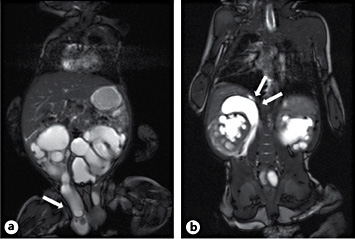

Urethral valves were ruled out by cystoscopy and a Pfannenstiel incision was performed. The right inguinal canal revealed a peritoneal sac and adjacent the megaureter corresponding to the paraperitoneal variant of inguinal herniation (fig. 2).

There are 2 variants of ureteroinguinal hernias, that is, a paraperitoneal and an extraperitoneal type. In the extraperitoneal type there is no hernia sac in contrast to the paraperitoneal type. To our knowledge, this paper is the first to report acute obstruction and kidney blow out due to this condition in an infant.